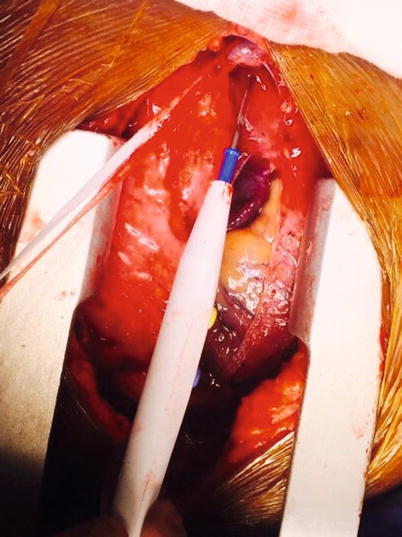

Fig. 37.5

Umbilical tape looped around the ascending aorta in order to aid retraction